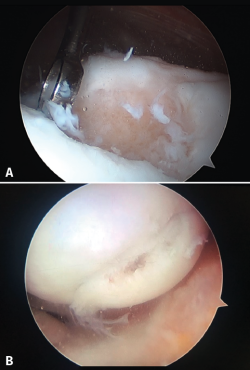

Although cartilage damage is most often of idiopathic or degenerative origin, joint cartilage injuries are also frequently caused by traumatisms (Figure 1A), i.e., joint trauma, followed by osteochondritis dissecans (OCD)(1,2) (Figure 1B).